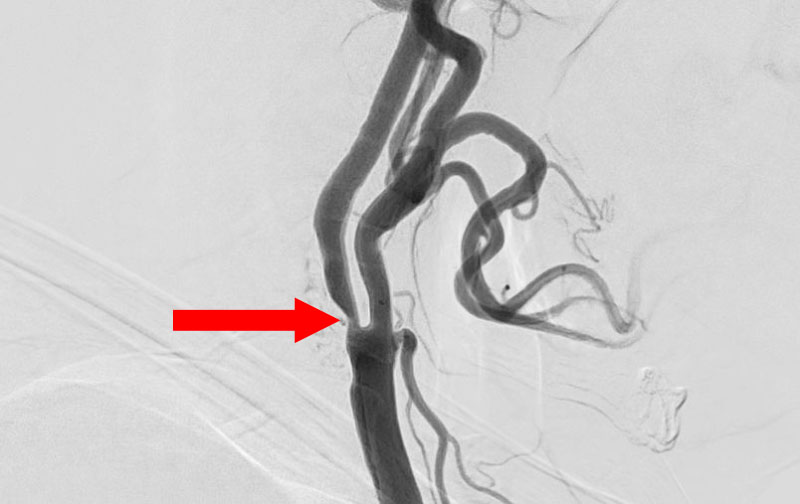

'25年11月

左内頚動脈脳動脈瘤

60代

大阪府の病院

No.1595 手術前

No.1595 手術中

No.1595 手術後